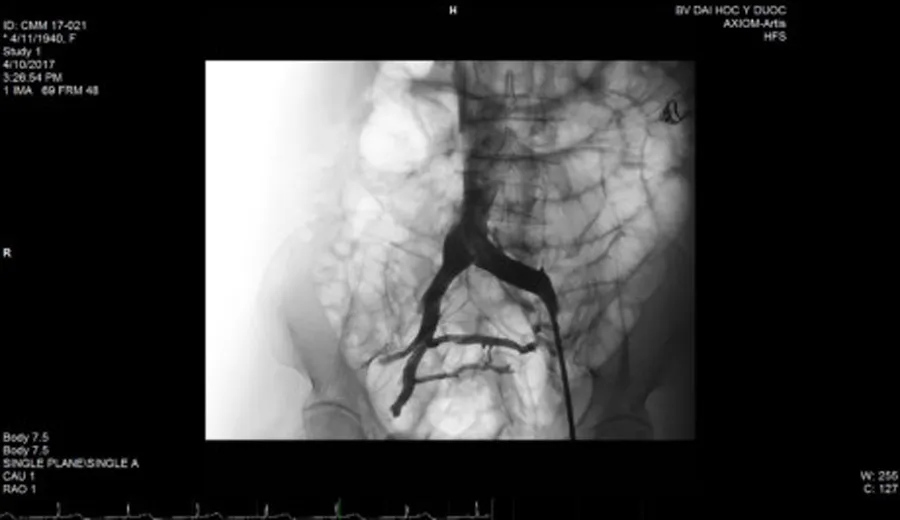

Thoát khỏi bệnh suy tĩnh mạch mạn  nhờ can thiệp nội mạch ảnh 1 Hình ảnh stent đặt trong lòng tĩnh mạch

Trước đây, hội chứng chèn ép tĩnh mạch chậu được điều trị bằng phẫu thuật. Đây là một phẫu thuật lớn, phức tạp, mất nhiều máu và gây đau đớn. Ngày nay, với sự phát triển của can thiệp nội mạch, hội chứng này có thể điều trị khỏi bằng cách nong bóng và đặt giá đỡ tĩnh mạch (stent). Chỉ qua một vết đâm kim ở vùng bẹn đùi, phần tĩnh mạch bị chèn ép sẽ được nong ra và sau đó được đặt stent vào lòng mạch. Khi dòng máu về tim không còn bị cản trở, các hậu quả do sự chèn ép gây ra sẽ không xuất hiện hoặc được cải thiện đáng kể khi đã xảy ra.